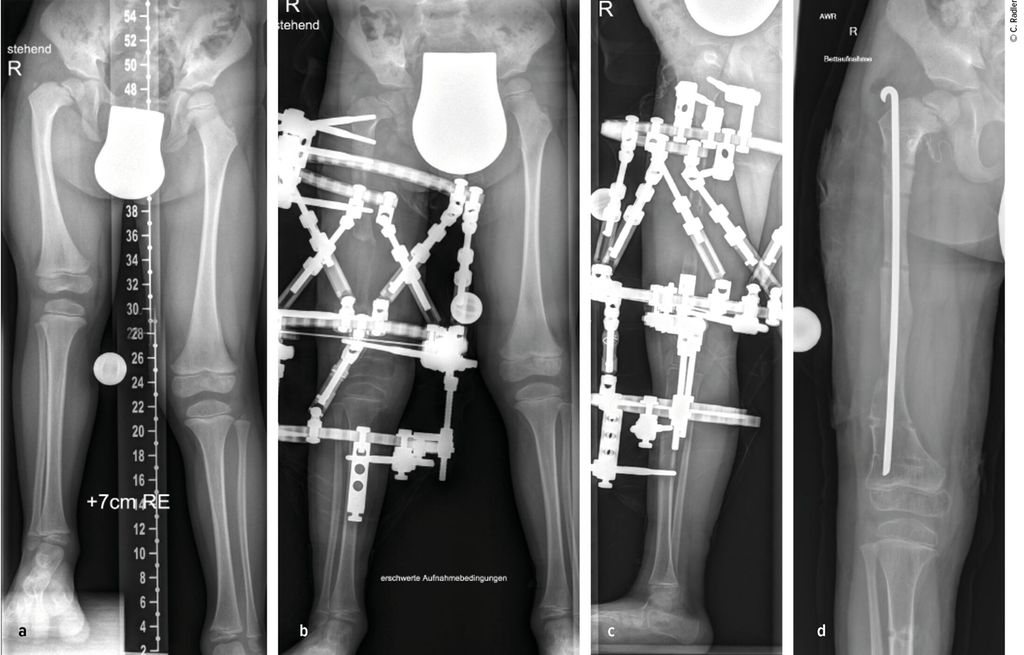

Im Rahmen dieser Operation können auch die Retrotorsion und der Schenkelhalsvarus korrigiert werden. Eine Verlängerung bei nicht optimal überdachter Hüfte führt meist zu einer Subluxation oder Luxation, was eine schwerwiegende Komplikation darstellt, die nur schwer und meist nicht folgenlos zu beheben ist. Auch bei älteren Patienten ist die Überdachung vor einer eventuellen Verlängerung zu überprüfen, wobei besonders ab dem 4. Lebensjahr eine Tripelosteotomie eine bessere Überdachung und Einstellung der Pfanne gegenüber einer Acetabuloplastik erlaubt (Abb.2).

Abb. 2:Versorgung eines kurzen Pfannendachs mittels Tripelosteotomie, um die Hüfte während der Verlängerung vor (Sub-)Luxation zu schützen